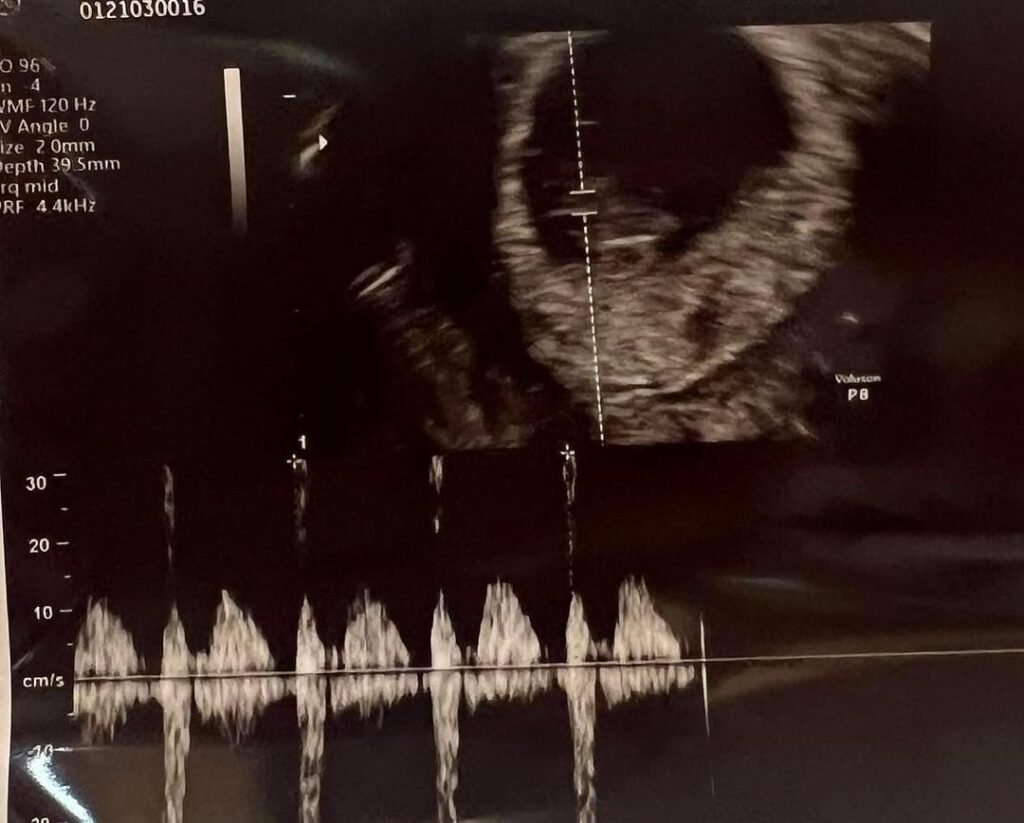

และล่าสุด พี่แจ็ค โพสต์ด้วยความอบอุ่นและความดีใจ ว่า วันนี้ได้ยินเสียงหัวใจเค้าครั้งแรก มันสะอื้นออกมาเอง มันอิ่มในใจ ใจมันฟูมาก ๆ คุณหมอบอก น้องโตเร็วมาก โตไวกว่าที่คุณหมอตั้งเกณฑ์ไว้ ลูกพ่ออออ ❤️❤️❤️❤️❤️❤️